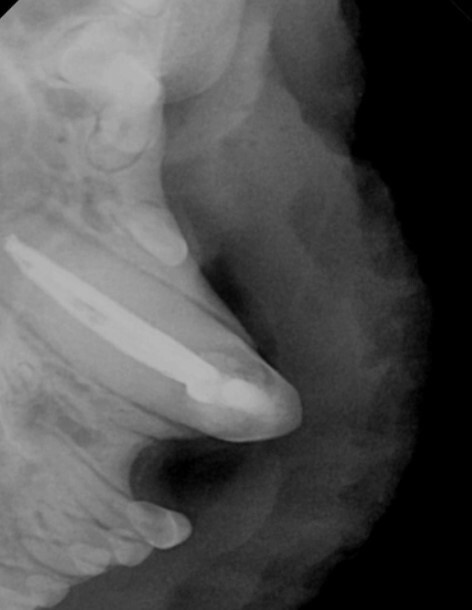

육안 검사상 얼굴 쪽에 아주 강한 충격을 받은 것으로

의심되는 상황이었습니다.

왼쪽 위 송곳니 깨짐과 아래턱뼈가 분리되어 있고

왼쪽 안구가 탈출되어 있는 안 좋은 상황이었습니다.

체력을 회복한 후 분리된 아래턱뼈를 결합하는

수술을 진행하였으나 분리된 채로 방치된 시간 동안

우측 턱뼈가 중앙으로 이동하여 위 어금니와 교합이

맞지 않는 상태였습니다.

아래턱뼈를 다시 정상 위치로 이동시키기 위한

교정 치료도 함께 진행되었습니다.

다행스럽게 턱관절의 탈구는 없는 것으로 확인되어

교정된 방향으로는 입을 닫는 것이 가능해 보였습니다.